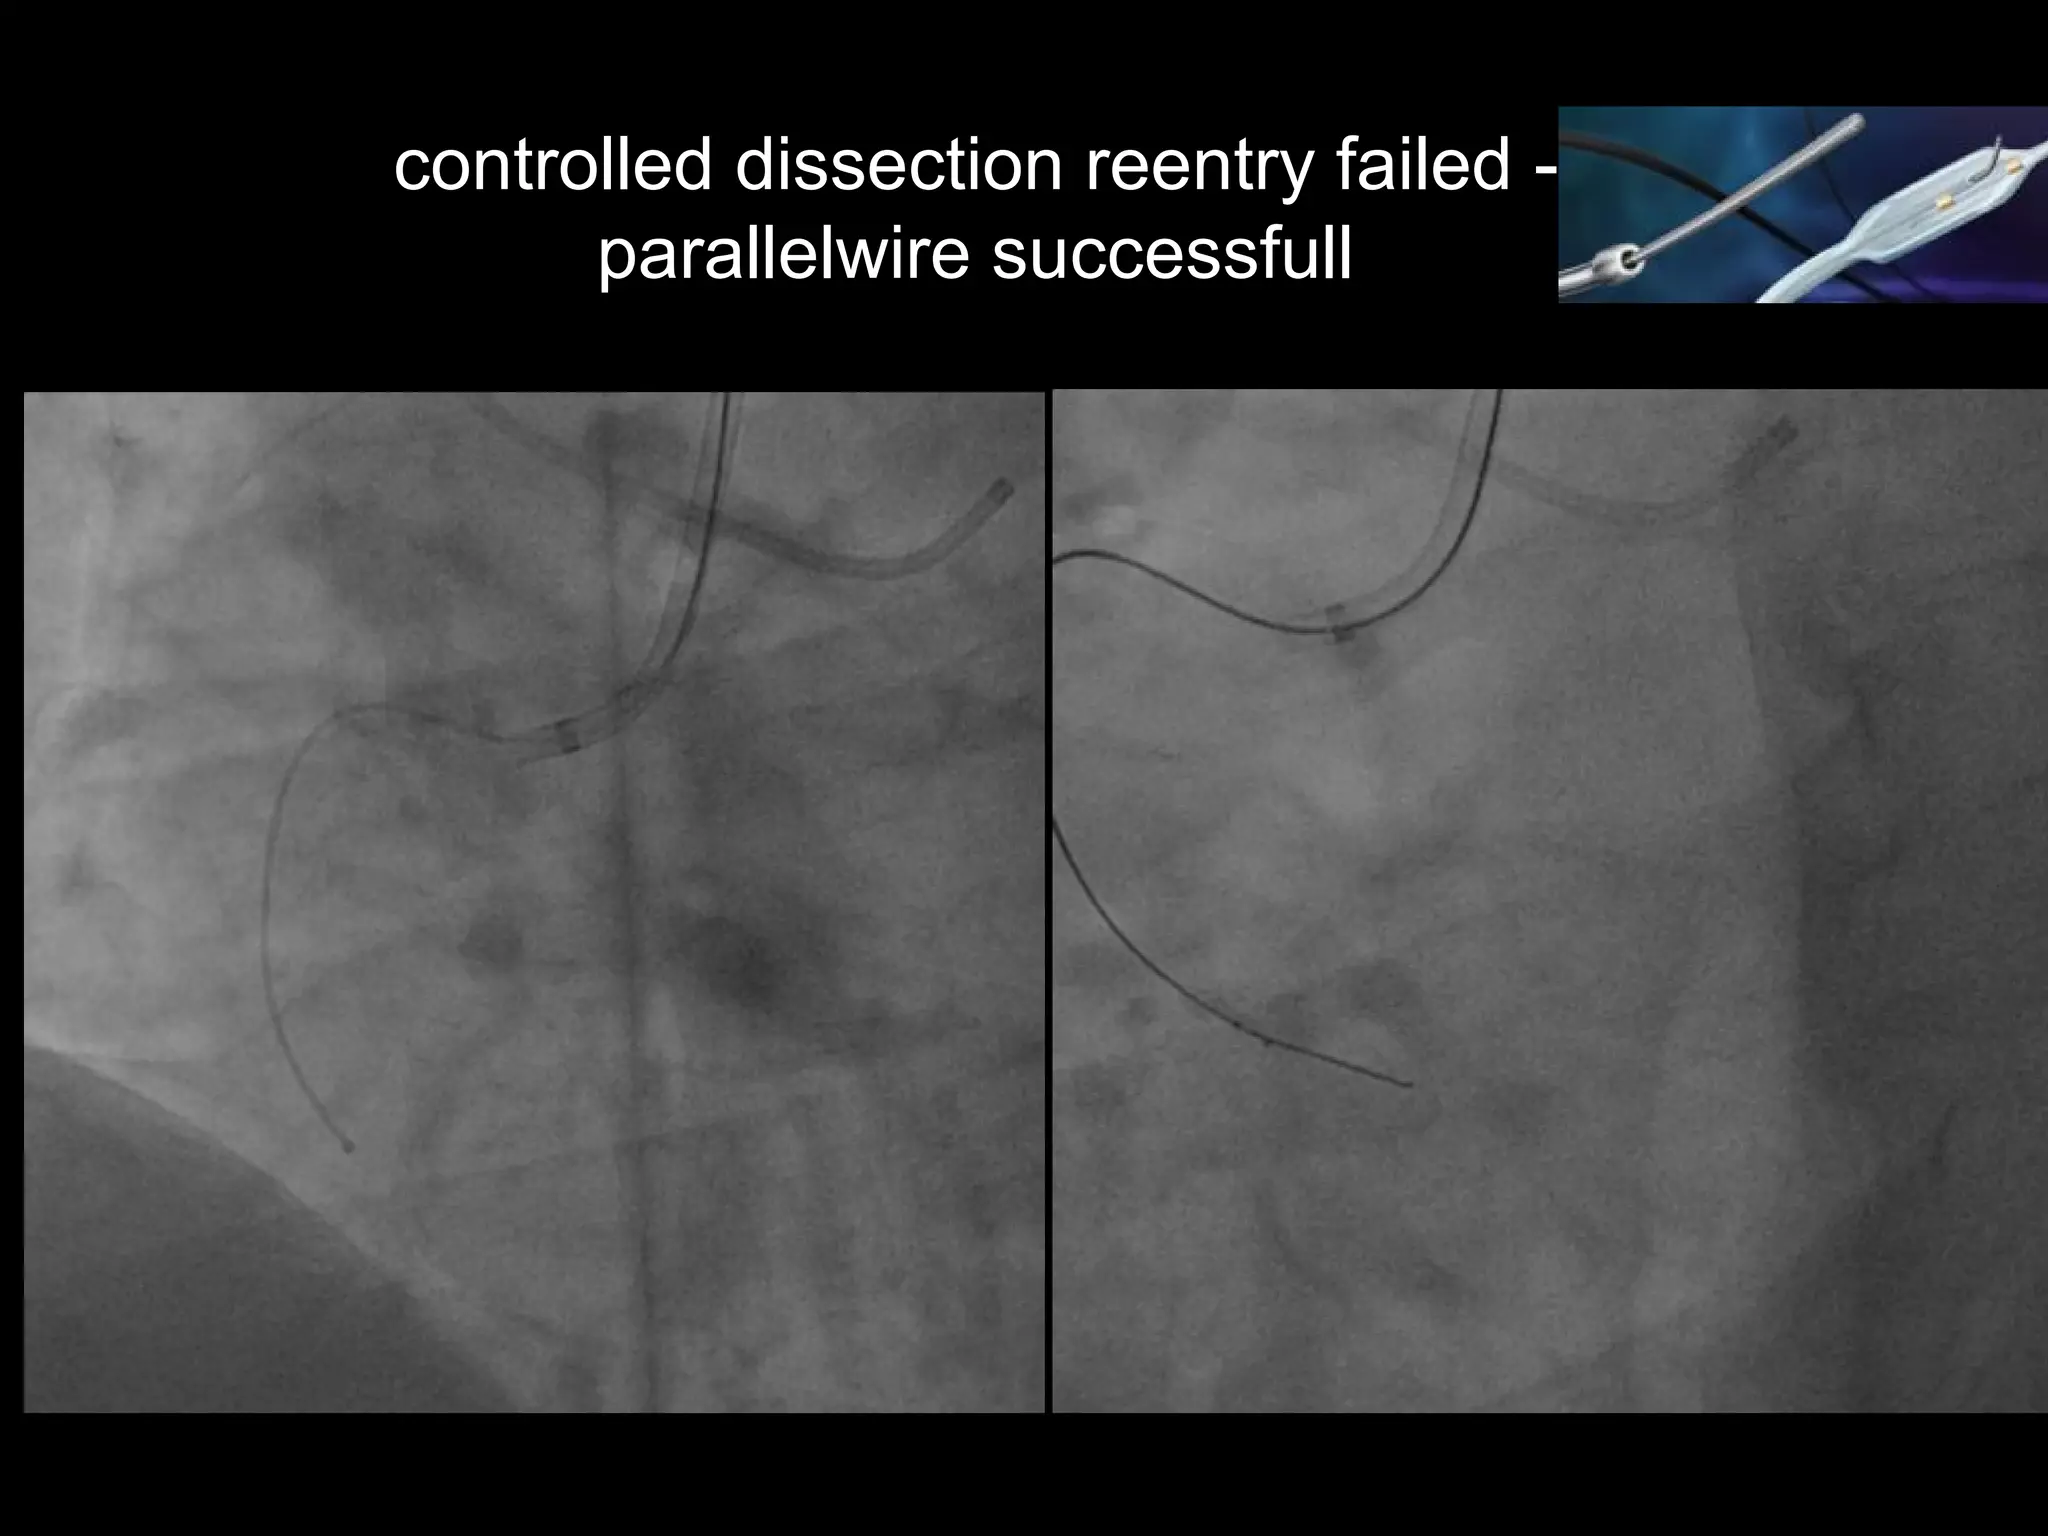

controlled dissection reentry failed -

parallelwire successfull